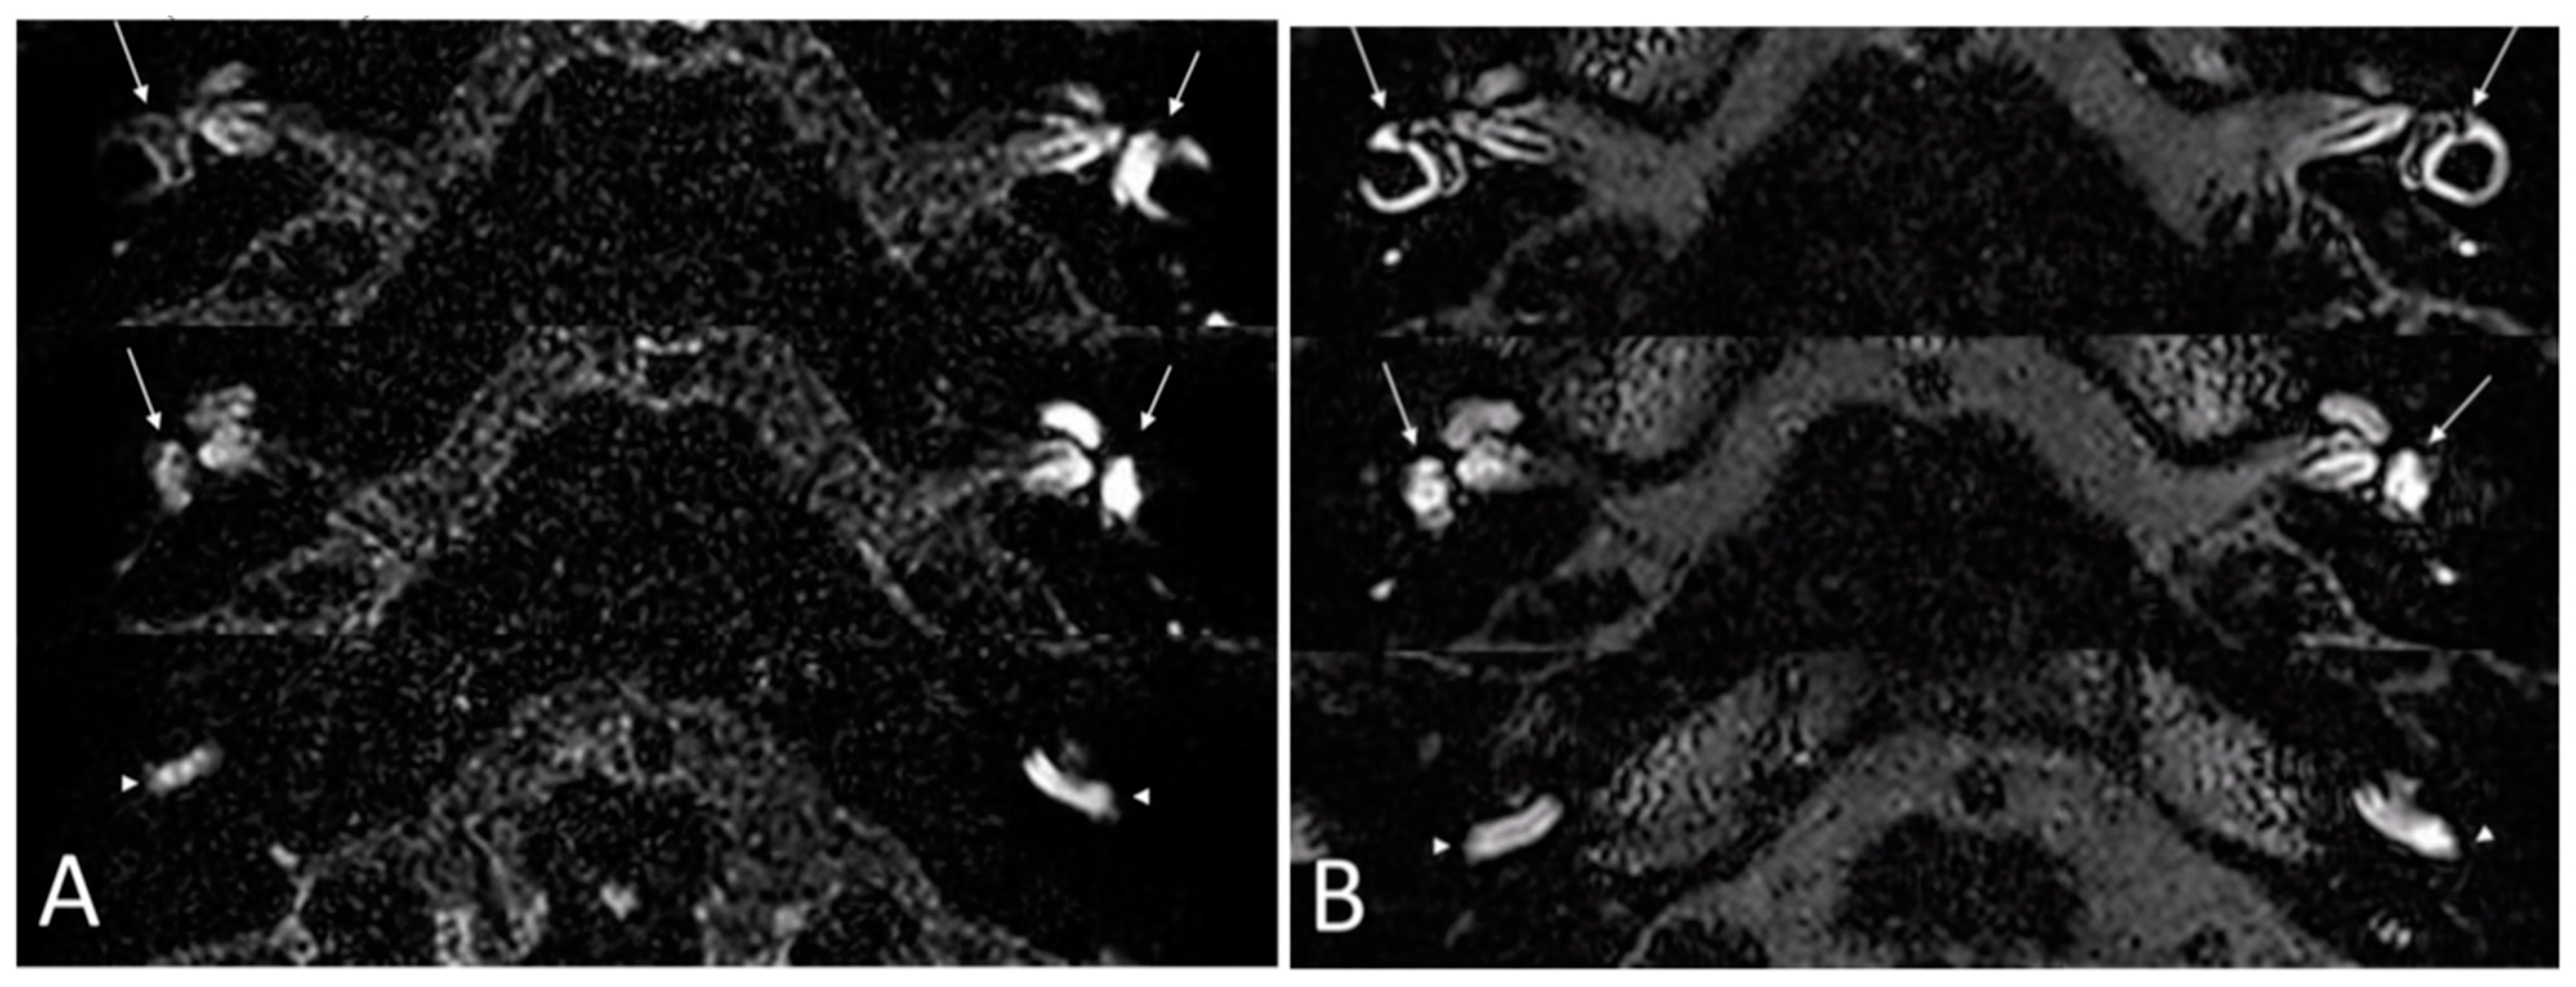

Imaging: all patients received an MRI with FLAIR sequences on the labyrinth before treatment and at 6 months. Before treatment, BLB impairment affected the cochlea in all ears and the vestibule in 11 ears. After treatment, a decrease of the BLB impairment was noticed in all ears, defined as a partial or total regression of enhancement of the labyrinth on injected FLAIR sequences. There was no aggravation of BLB impairment during the clinical outcome in five ears. In six ears, an improvement of BLB impairment was seen without any improvement of the PTA. In two ears, there was no improvement in BLB impairment. Figure 2 illustrates an example of the improvement of the delayed FLAIR sequences on the labyrinth after the 6-month treatment period.

Figure 2.

Delayed 3D-FLAIR MRI sequences. (A) Before treatment. Enhanced signal of the left vestibule (arrows) and the basal turn of the cochlea (arrowhead) compared with the right side. (B) At 6 months: symmetrical enhancement of the vestibule (arrows) and the basal turn of the cochlea (arrowhead).